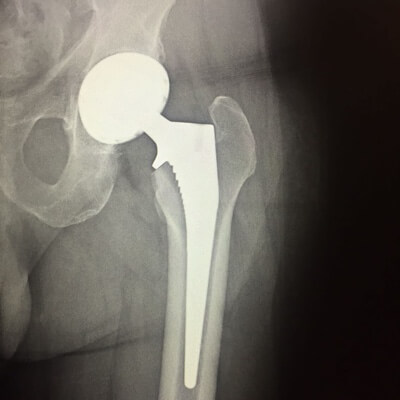

LA HANCHE

Arthroplastie

Remplacement prothétique des surfaces de l'articulation de la hanche (prothèse totale de hanche).

Pour un bilan concernant l’arthrose de la hanche (coxarthrose) des radiographies standards sont l'examen de choix. Pour la recherche d’autre pathologies, l'arthroscanner ou l’irm sont à discuter.